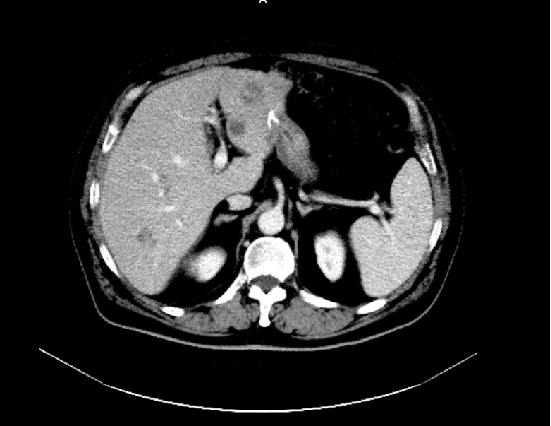

2019-06:

2020-05:

2019-06:

2020-05:

胸腹盆增强CT(2020-05-08):直肠癌治疗术后,左下腹造瘘术后,肝脏多发转移较前增多增大,双肺气肿,主动脉及冠状动脉硬化,双肾囊肿